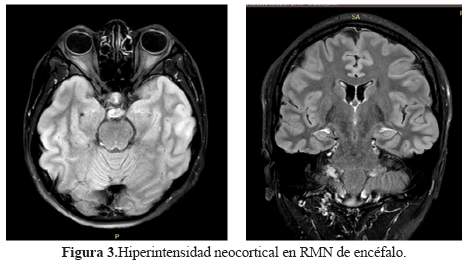

Los exámenes paraclínicos concuerdan con las diferentes series reportadas. Si bien el paciente presentó alteraciones epileptiformes en el electroencefalograma, no se encontró delta brush, patrón que se ha descrito generalmente en estados comatosos (14). En cuanto a las neuroimágenes, entre 45% a 77% de casos la resonancia magnética (RMN) permanece normal (figura 3). Entre los anormalidades más frecuentes figuran las hiperintensidades en el lóbulo temporal mesial, multifocales o lesiones inespecíficas en sustancia blanca (1,2). En el paciente sólo se evidenció signos de edema cortical inespecífico. Respecto a las anormalidades en la LCR entre 61 y 91% de encefalitis contra NMDAR presentan pleocitosis linfocítica (1,2); y es más probable encontrar estas alteraciones en estadios tempranos de la enfermedad (2).